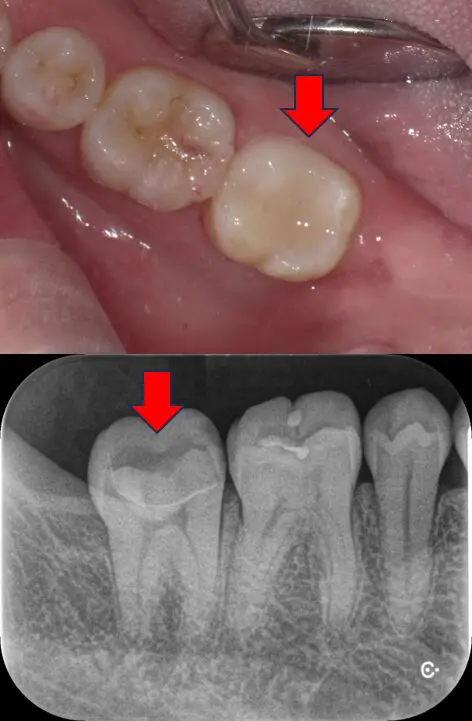

つくば市在住、「神経を残したい」深い虫歯を1回でセラミック修復治療した症例|40代男性・セレック治療

| 主訴 | 歯がしみる 神経をなるべく残したい |

|---|---|

| 診断名 | 深い虫歯(象牙質う蝕・C2) |

| 年齢・性別 | 40代 男性 |

| 治療期間・回数 | 1日 1回 |

| 治療方法 | セレックシステムによるセラミック修復 |

| 費用 | 88,000円(税込96,800円) |

| メリット | ・1日で治療が終わり、痛みも出づらい ・歯の神経に炎症が起こらず、残せる可能性が高くなる ・詰め物の接着力が高くなる |

| デメリットを・注意点 | ・保険外なので費用が高くなる。 ・歯ぎしり、くいしばりで欠けてくる可能性 |